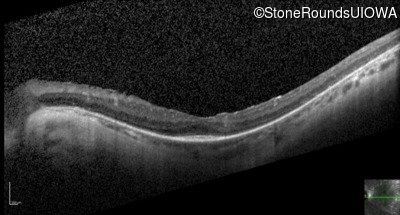

Optical Coherence Tomography - Right - 20/50 +1

Exemplar / OCT Stack

OCT Stack